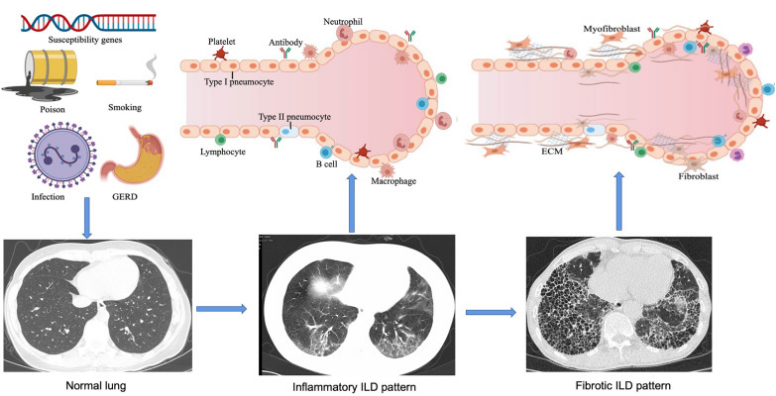

CTD-ILD发病机制

遗传易感人群在受到如吸烟、化学物质暴露、感染、胃食管反流病等外部因素作用下,引起肺部损伤,尤其是肺上皮细胞损伤以及异常修复,引起肺泡巨噬细胞活化,中性粒细胞募集和氧化应激,随着时间的推移,ECM增加,进而导致肺间质纤维化。早期可有肺泡炎的表现,随着疾病进展,会出现肺泡间隔的增厚,胶原纤维的沉积,毛细血管床显著减少,出现肺泡结构的改变以及纤维化。间质性改变最初可能表现为免疫异常和炎症损伤,疾病发展后期会引起肺组织纤维化。